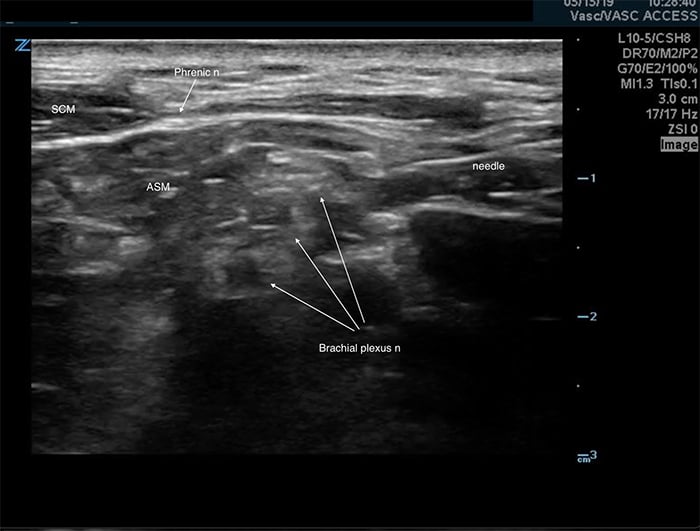

- The ipsilateral phrenic nerve overlies the anterior scalene muscle near the interscalene space. (Figure 4) It is affected during an interscalene nerve block,5 suspected to occur via anterior spread of the anesthetic. Although this complication is associated with a significant reduction in pulmonary function tests,5,6 it is well tolerated in most healthy patients.5,6 Care should be taken in patients with respiratory compromise or underlying lung disease.

Figure 4. Phrenic nerve

Figure 3. Needle placement for the interscalene block

- In-plane approach from the posterior side of the probe is preferred.

- Insert the block needle 5 mm at ~30 degrees to the skin surface at the posterior side of the probe.

- Identify the needle tip and ensure it is always in view.

- Advance the needle toward the plexus.

- Pass through the prevertebral fascia, which is a dense, echogenic layer overlying the scalene muscles that resists needle penetration. It may produce a “click” felt in the needle when passed through.

- Slowly advance the needle towards the plexus.

- Goal is to inject between elements of the plexus.

- Care is taken not to violate the individual elements of the plexus.

- Common target is between the top and second trunk.

- Once movement of the needle causes movement on the plexus, injection may begin.